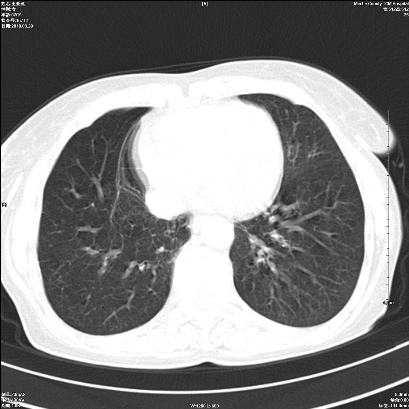

ct所见:右肺上叶肺不张,呈软组织密度影向肺门区聚拢,其内可见含气段支气管及细支气管影,病灶内尚可见钙化结节。右肺上叶支气管狭窄,段支气管壁可见钙化。右肺下叶背段、右肺中叶见不规则小片絮状影及纤维条索影,形态较僵硬。右肺中叶胸膜旁可见多个小结节影。纵膈内见钙化淋巴结。

分析:右侧胸廓及右肺体积缩小,说明病变时间比较长了,应该是有数年的时间了,如果是短期内出现的肺不张,只会引起纵膈向患侧移位,而不会引起胸廓的塌陷。不张的肺组织内可见含气支气管影,说明右肺上叶支气管没有完全中断,只是狭窄。右肺中叶、下叶散在不规则病灶,部分呈纤维化改变。纵膈内的淋巴结大部分钙化。因此,本例给我的感觉良性病变的可能是大。

结论:考虑右肺上叶支气管内膜结核合并右肺上叶肺不张;右肺中叶、下叶陈旧性肺结核改变。